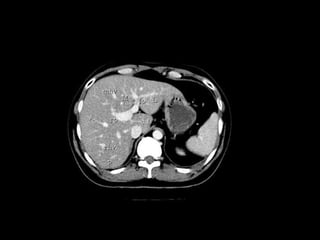

Radiographers use medical imaging equipment like X-rays and MRIs to produce images of patients' internal structures and organs. They are responsible for positioning patients, operating scanning machines, and ensuring quality images. Radiographers must have strong attention to detail, excellent communication skills, and the ability to work well under pressure to accurately capture anatomical features and diagnose any abnormalities.